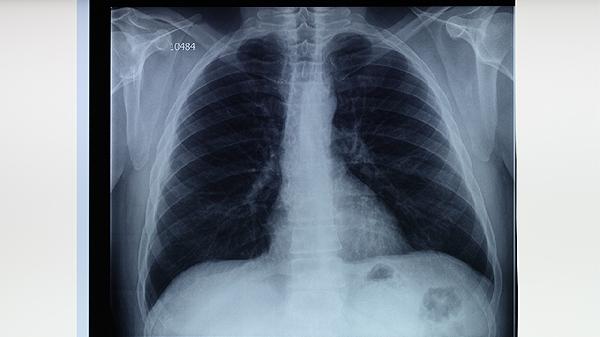

肺结核患者出现淋巴结肿大主要与结核菌的淋巴扩散有关。结核菌侵入人体后,可能通过淋巴管迁移至淋巴结,引发局部免疫反应,导致淋巴结增生、干酪样坏死等病理改变。这类肿大的淋巴结质地较硬,初期可活动,后期可能粘连成团,部分患者伴随低热、盗汗、消瘦等全身症状。胸部影像学检查常显示肺门或纵隔淋巴结肿大,确诊需结合结核菌素试验、淋巴结穿刺活检等。